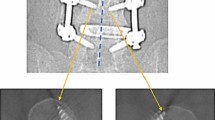

Although there is no gold standard for assessing screw placement, CT has virtually assumed this role [20, 21]. The kappa statistic resulting from this data is strong and (K = 0.8042) suggests substantial to near-perfect agreement between MRI and CT, see Figs. 3 and 4. Undeniably, none of the CT images were rendered poorly enough as to disable the interpreter from assessing the images. Each image gave visual, diagnostic-level confidence in determining the placement of the screw [11].

MRI of L4 with markup. Scanning Parameters: Siemens Avanto, T1, TE:10, TR:523, ETL:5, window 1707 level 810. When viewed in conjunction with Fig. 4, these comparison images show a strong level of agreeability between MRI and CT scans of the same vertebral level in the same patient

CT of L4 with markup. Scanning parameters: Siemens sensation 64, 140 kV, 390 mA, 1000 ms, 135DFOV, 1 mm, window 1500 level 450. Note—the CT image calliper measurements have not been displayed well on the image output due to colour, and the measurements relating to standard anatomical position are 7.4 mm, right, and 7.9 mm, left. The right screw length is 44.3 mm and the left screw length is 44.1 mm. When viewed in conjunction with Fig. 3, these comparison images show a strong level of agreeability between MRI and CT scans of the same vertebral level in the same patient